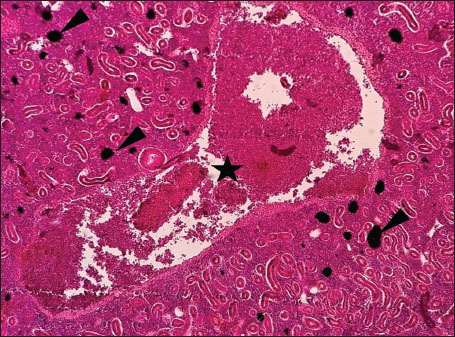

Fig. 3. Histopathology of the kidney in an adult L. sceleratus showing dilated and congested blood vessels (star) and severe MMC proliferation (head arrows). ×40 H&E.

ABSTRACTBackground: The Mediterranean Sea has undergone significant ecological changes in recent decades, partly due to the introduction of non-native species. Lagocephalus sceleratus is an invasive Lessepsian species widely distributed in the Mediterranean, increasingly abundant along the Libyan coast, and potentially exposed to chronic environmental stressors. This species represents an important model for baseline pathological assessment in newly colonized marine environments. Aim: This study provides a descriptive histopathological assessment of kidney and gill tissues in adult L. sceleratus to document baseline tissue alterations without inferring direct environmental or pollution-related causation. Methods: A total of 150 adult specimens were collected from four Libyan coastal locations. Tissues were processed using standard histological techniques and evaluated semi-quantitatively (+, ++, +++) for lesion severity. Lesion severity grades were converted into ordinal numerical data and summarized using descriptive statistical approaches only. Results: Kidney tissues exhibited tubular degeneration, Bowman’s capsule dilatation, vascular congestion, extensive melanomacrophage centers (MMCs), and inflammatory lesions. Gill tissues showed disorganization of secondary lamellae, epithelial hyperplasia, edema, aneurysmal dilatations, vascular congestion, and MMC proliferation, some of which were associated with histologically observed parasitic structures. Conclusion: The observed alterations represent descriptive baseline tissue changes and should not be interpreted as direct evidence of pollution or specific environmental stressors. These findings provide reference data for future comparative pathological and ecological studies. Keywords: Lagocephalus sceleratus, Kidney, Gills, Histopathology, Melanomacrophage centers, Invasive species, Mediterranean Sea. IntroductionIn recent decades, the Mediterranean Sea has undergone profound ecological changes driven by the arrival and establishment of non-native marine species. Among these, Lagocephalus sceleratus has emerged as one of the most impactful Lessepsian migrants, due to its rapid geographic expansion, high ecological adaptability, and the presence of the potent neurotoxin tetrodotoxin in its tissues. This species has been widely documented to alter local fish communities, affect fisheries, and pose public health risks, making it an important target for biological and environmental assessment across the region (Katikou et al., 2022; Christidis et al., 2024). Fish are widely recognized as sensitive biological organisms in aquatic ecosystems, particularly in coastal habitats that are exposed to anthropogenic pressures such as industrial effluents, agricultural runoff, and untreated wastewater (Pinna et al., 2023). Among fish organs, the gills and kidneys are commonly regarded as sensitive to environmental stress, as they respond to physiological and pathological changes under environmentally suboptimal conditions. The gills, due to their large surface area and continuous exposure to surrounding water, are often the first tissues to exhibit structural alterations when fish encounter pollutants (Shahid et al., 2022). Histopathological changes in gills observed in polluted environments include epithelial lifting, lamellar fusion, hyperplasia, increased mucous cell density, and focal necrosis, which collectively reflect early physiological stress and potential compromise of respiratory function (Osman, 2010; Shahid et al., 2022). Similarly, the kidneys play crucial roles in osmoregulation, excretion of metabolic waste, and detoxification, making them highly vulnerable to chronic or systemic toxic effects (Wahidi et al., 2025). Documented renal lesions associated with chemical exposure include tubular deterioration, glomerular shrinkage, interstitial edema, and infiltration of inflammatory cells. These structural alterations often coincide with underlying biochemical disruptions, such as oxidative stress, impaired detoxification pathways, and activation of apoptotic mechanisms (Bernet et al., 1999; Authman, 2015). Despite the growing body of research on the ecological and toxicological implications of L. sceleratus, detailed histopathological assessments of this species remain scarce, especially in the southern Mediterranean basin, where environmental conditions and pollution profiles may differ from those in other regions. To date, detailed tissue-level studies of L. sceleratus from the southern Mediterranean are lacking, which limits the understanding of how this invasive species responds physiologically to local environmental stressors (Shakman et al., 2019; Ulman et al., 2021; Mohmmed et al., 2023). Accordingly, the present study aims to provide a comprehensive descriptive evaluation of histopathological changes in the kidneys and gills of L. sceleratus. The study is designed as a baseline histopathological assessment, focusing on tissue-level alterations without establishing causal links to environmental pollution or physicochemical stressors. By documenting structural aberrations and pathological features, this study contributes reference data for future monitoring and comparative studies in Mediterranean coastal ecosystems. Materials and MethodsSample designA total of 150 adult specimens of L. sceleratus, including both sexes, were collected from four Libyan coastal locations: Talamitha (n=39), Susah (n=34), Ain El-Ghazala (n=30), and Khalij Al-Bambah (n=47). Fish ranged in total length from 51 to 66 cm and in weight from 1.5 to 3.5 kg. Only apparently healthy adults were included, while juveniles were excluded to avoid age-related histopathological variation. Sampling was conducted opportunistically with assistance from local fishermen. All specimens were collected within a comparable seasonal window to minimize seasonal histopathological variability. Sex was recorded when possible; however, sex-based histopathological comparisons were not performed, as this was beyond the descriptive scope of the study. Fish were transported on ice at +4°C and examined in the Pathology Laboratory, Faculty of Veterinary Medicine, Omar Al-Mukhtar University (Mohmmed et al., 2023). Specimens were collected from a range of depths (0.5–70 m), with the majority from shallow waters (<10 m) and a subset (approximately 50 fish) from deeper locations (>30 m). Environmental physicochemical parameters such as temperature, salinity, and dissolved oxygen were not measured; therefore, no direct associations between histopathological findings and environmental variables were assessed. Tissue processing and histopathological examinationTissue specimens were fixed in 10% neutral buffered formalin for 24 hours. Following fixation, the samples were transferred to 70% ethanol for storage at room temperature. Subsequently, the tissues were processed for routine histopathological examination following standard procedures (Paul and Chanda, 2017). Paraffin embedding was performed, and 5 µm-thick sections were prepared using a microtome. Sections were stained with hematoxylin and eosin (H&E) and examined under a light microscope. Photomicrographs of representative lesions were captured using a high-resolution digital camera. Histopathological alterations were evaluated using a semi-quantitative scoring system adapted from Hose et al. (1996), Moshaie-Nezhad et al. (2021), and Alshailabi et al. (2023), where lesion severity was graded as mild (+), moderate (++), or severe (+++). Lesion severity grades (+, ++, +++) were converted into ordinal numerical values (1–3) for descriptive summarization of lesion severity. Due to the descriptive baseline nature of the study and the absence of a reference control group, inferential statistical comparisons were not emphasized or applied. Lesion severity scores were therefore summarized descriptively to avoid overinterpretation of the findings. Scoring was performed independently by two experienced observers, and representative lesions were confirmed across three sections per organ to ensure consistency. Tissues with visible parasitic structures were described separately from non-parasitized tissues to avoid conflating parasite-associated lesions with non-specific tissue alterations. The functional implications of the observed lesions were interpreted in accordance with Flores-Lopes and Thomaz (2011). Ethical approvalAll animal experiments conducted in this study were approved by the Ministry of Higher Education & Scientific Research and the Libyan National Committee for Biosafety & Bioethics, Libya. All procedures were performed in accordance with the relevant ethical guidelines, with session number 21/CH/25, dated 26/05/2021. ResultsHistopathological examination of the kidneyHistopathological examination of the kidney tissues of L. sceleratus revealed multiple alterations. Prominent melanomacrophage centers (MMCs), necrotic areas, dilatation of Bowman’s capsules, and vacuolar degeneration were observed (Fig. 1), associated with interstitial lymphohematopoietic tissue (Fig. 2). Dilated and congested blood vessels and extensive MMCs were also noted (Fig. 3). Renal degeneration surrounding lymphohematopoietic tissue, large clusters of MMCs, and thickened, congested vessel walls within fibrotic areas were evident (Fig. 4). Atrophic renal degeneration with necrotic and vacuolar changes was observed (Fig. 5). Severe inflammatory infiltration of lymphatic cells and granulomas with necrotic centers, surrounded by fibrous tissue, was detected (Figs. 6–7).